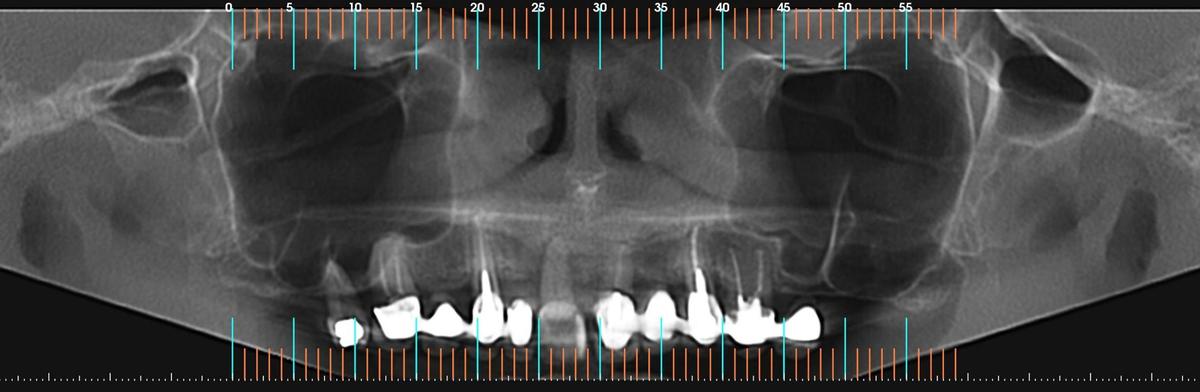

PRÓTESE TOTAL FIXA EM IMPLANTES

M.C.R.B.S.